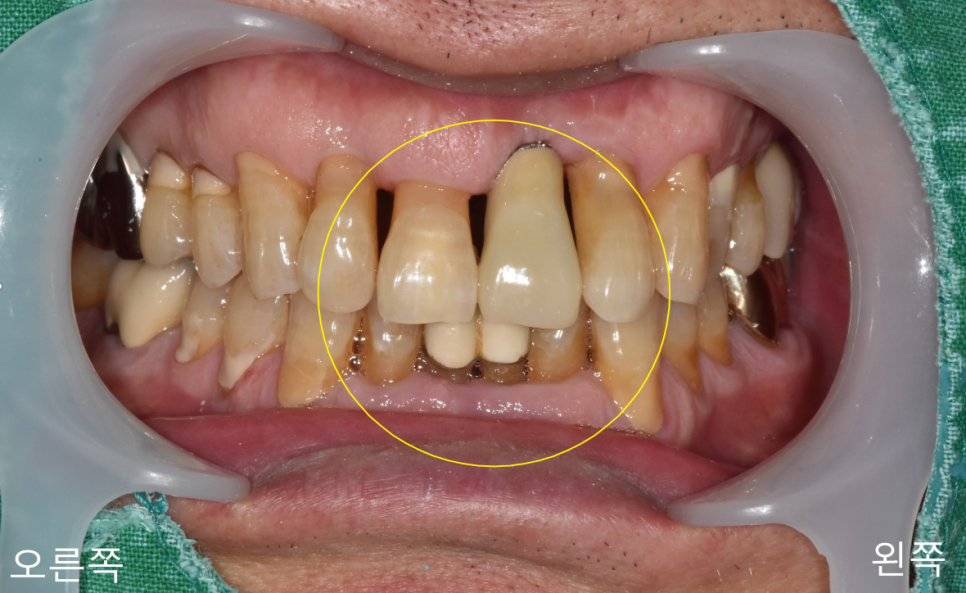

위에 사진을 보게 되며

치주가 위로 많이 올라가

치근의 노출된 부분과 치근 우식이 보입니다.

치아의 목 부분에 우식이 많이 생기기 때문에

치아가 구조적으로 취약해질 수 있고

우식이 심해지는 경우

치아가 부러지는 경우도 생길 수 있습니다.

또한, 치근이 노출되면서

시림 증상도 크게 나타날 수 있습니다.

충치만 생기셨다면 치료를 할 수 있지만

이미 치조골과 잇몸 퇴축이 있고

치아의 동요도가 있는 상태라 발치가 필요한 상황이었습니다.

치근에 우식이 생기는 경우 신경치료와 보철치료를 해도

경과가 좋지 않은 경우가 발생하니 자주 검진을 받는 게 중요합니다.

교합 면 쪽에서 바라봤을 때

앞니의 치조골이 푹 들어간 모습을 볼 수 있습니다.

이런 경우

임플란트 식립 시 고정이 잘 안 되는 경우가 발생하기도 합니다.